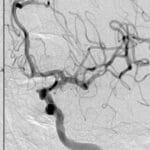

Topic: Cerebral Hyperperfusion Syndrome Author: Ayah Bozeyeh Editor: Ihda Bani Khalaf Reviewer: Ethar Hazaimeh Keywords: Blood flow, Stroke, Pressure, Circulation, Autoregulation, Cerebrovascular disease Overview Cerebral Hyperperfusion Syndrome (CHS) is a rare but potentially devastating complication characterized by an abnormal and excessive increase in cerebral blood flow, which can lead to neurological deterioration, brain injury, and even death. It often occurs following revascularization procedures that aim to improve cerebral circulation, such as intracranial angioplasty, stenting, carotid endarterectomy, and carotid artery stenting. [1] As the utilization of these procedures increases, particularly for patients at high risk for ischemic stroke, there is a […]